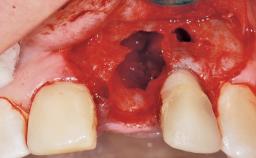

Immediate Flapless Placement of an Implant in a Maxillary Left Central Incisor Site

A 42-year-old female patient was referred to our clinic at the School of Dentistry of the University of São Paulo in November 2004, presenting a deficient restoration in the upper left central incisor. The clinical examination revealed no gingival retraction or any signs of gingival inflammation and, therefore, previous periodontal treatment was not considered. The patient presented a high lip line at full smile and a thin tissue biotype. This combination characterized a high-risk situation from an anatomic point of view, which required careful preoperative planning and cautious surgical execution.

Placement Protocol Immediate implant placement

Tooth Site Maxillary incisor or canine

Socket Morphology Single-root socket

Socket Integrity Sufficient, with intact bone walls